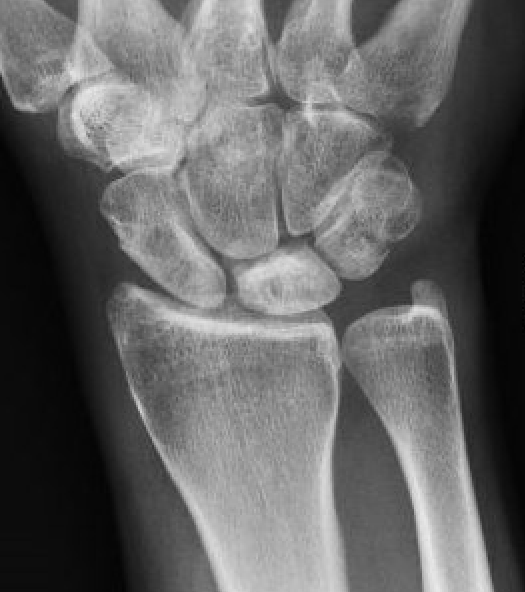

Xray

Progressive changes of AVN

- sclerosis

- fragmentation / fracture / flattenging

- midcarpal collapse: scaphoid flexion / capitate descent

- radiocarpal and midcarpal osteoarthritis

Lichtmann Classification

Stage I

- xray normal

| Stage II | Stage IIIA |

| Sclerosis |

Collapse / fragmentation Normal carpal height |